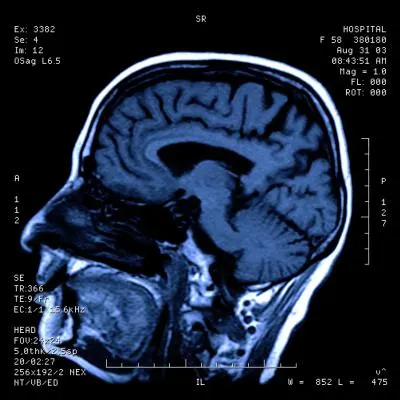

CT Brain in Navi Mumbai | Henotic Diagnostics

Looking for a CT Brain scan in Navi Mumbai? At Henotic Diagnostics, we provide advanced and accurate brain CT scans. Moreover, our high-resolution imaging helps detect strokes, head injuries, tumors, hemorrhages, and neurological conditions with precision. In addition, our expert radiologists and modern equipment ensure quick, detailed reports. We serve Kharghar, Panvel, Belapur, Vashi, Nerul, Airoli, Kamothe, Taloja, Kalamboli, and nearby areas. Therefore, for affordable care and reliable results, choose Henotic Diagnostics today.